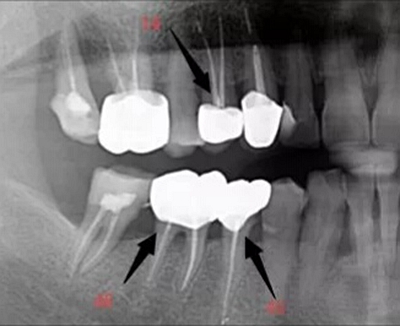

1.根管引導(dǎo)劑:新的根管引導(dǎo)劑,能快速溶解細(xì)小閉鎖根管口,溶解潤(rùn)滑根管壁,使根管擴(kuò)大器械安全,快速到達(dá)根尖位置。

2.半導(dǎo)體激光加碘仿液,高效殺死根管和側(cè)付根管內(nèi)感染細(xì)菌,激光根管及牙周綜合完善消毒,光照點(diǎn)約600~800度瞬間高溫使根管內(nèi)感染組織、蛋白質(zhì)、細(xì)菌、血液殘留和碘仿液瞬間氣化,達(dá)到快速滅菌效果。

3.定向骨誘導(dǎo)劑的使用,使生物牙產(chǎn)生骨結(jié)合,增強(qiáng)了患牙穩(wěn)固度,提高了咬合力。

4.3D液體牙膠充填劑,可以有效到達(dá)根尖部及側(cè)付根管,使根管內(nèi)不留死腔,有效封閉側(cè)付根管和根尖孔,提高了治愈率。

5.激光+根管及主要側(cè)副根管的均質(zhì)3D充填+定向骨誘導(dǎo)結(jié)合,徹底解決了擴(kuò)大(原來(lái)難找、難擴(kuò))、消毒(原來(lái)有效率<80%)及骨結(jié)合問(wèn)題,使牙髓及牙周得到了比傳統(tǒng)方法更有效的治療。